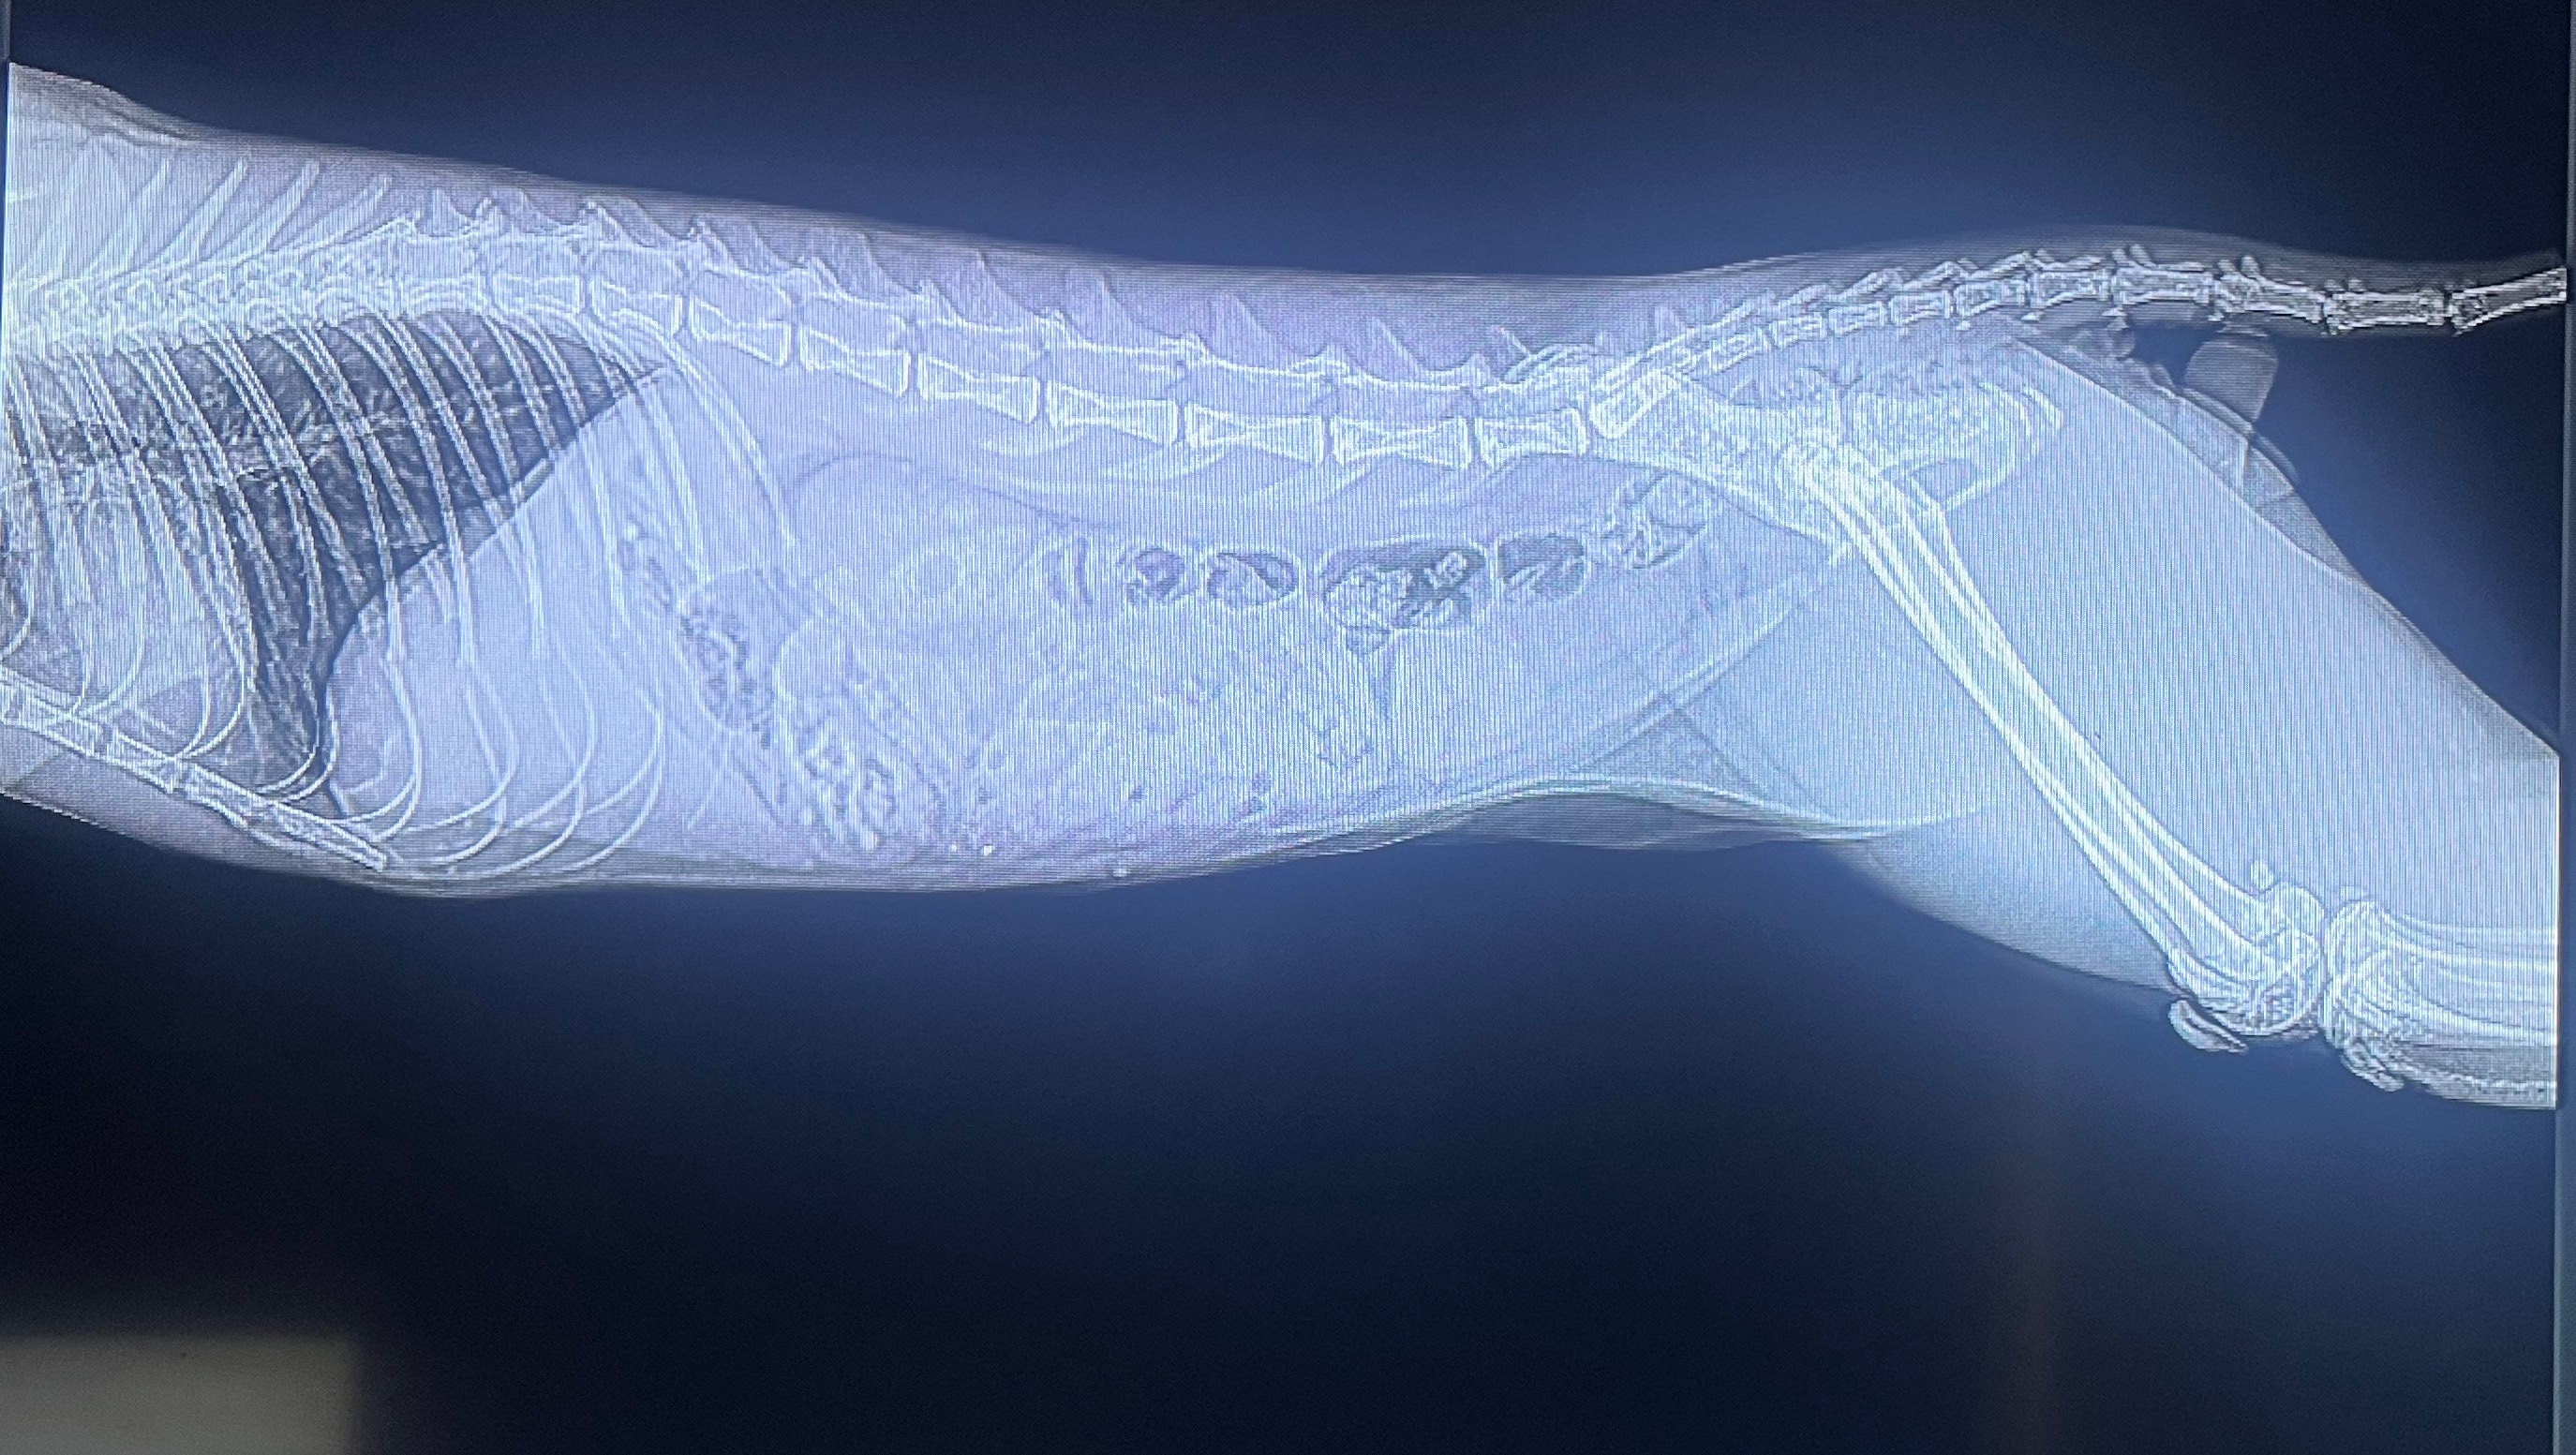

The X-Ray Came Back, And It Wasn’t Good. Kage Was Completely Blocked. His Stomach Was Full Of Hair Ties, And All Kind Of Other Things He Might’ve Swallowed Like Food, Hair, ETC. They Were Beginning To Bunch Up Because Of How Long They Were In There, Getting Stuck In His Small Intestines. The Next Step Was To Send The X-Rays To A Radiologist Who Could Confirm Exactly What He Needs, But It Most Likely Meant He Needed Surgery.

His Family Was Now At A Loss. They Couldn’t Afford To Get The Next Step He Needed To Recover. They Sadly Had To Take Kage Back Home With Nothing But A Prayer That He’d Be Okay Until They’d Be Able To Get More Money To Get The Next Step He Needs To Feel Better. All They Had Were X-Ray Photos, And A Medication That The Hospital So Kindly Gave Them To Maybe Help In Any Way Possible.